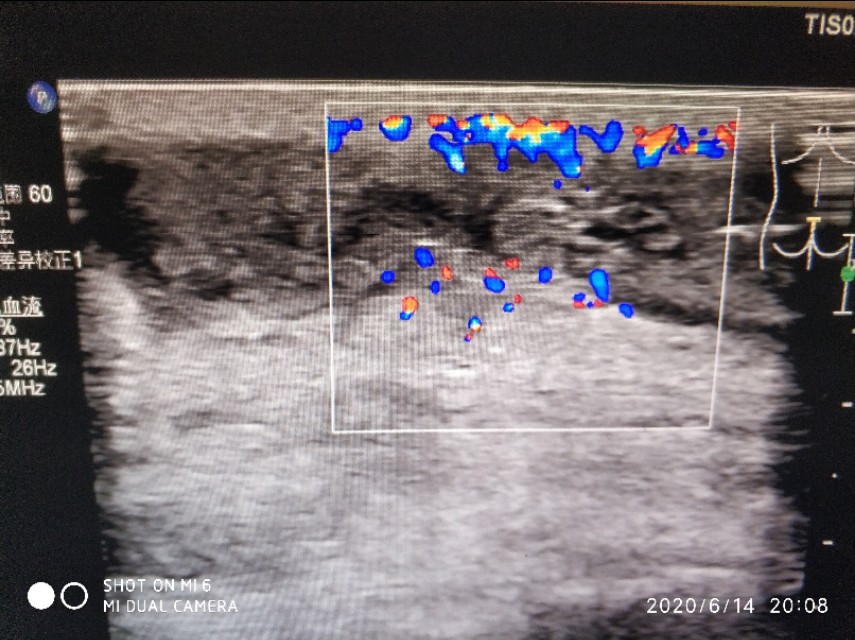

这是我们科长做的,可以看到包块周围血流还是挺丰富的,提示可能有肉芽组织增生,里面有几根条带状的毛发回声。